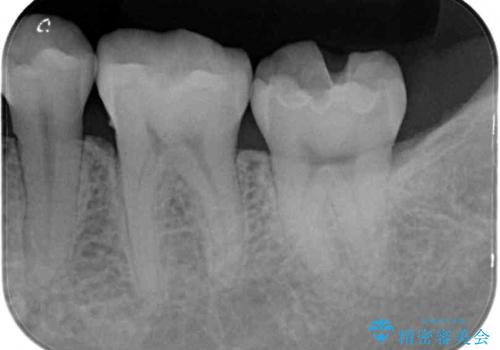

- 下の奥歯に虫歯ができてしまったとのことで来院された患者様です。

他にも気になる歯はありましたが、急を要する1歯のみをセラミックインレーにて修復治療を行うこととしました。

奥歯において、隣の歯と接触する部分に虫歯が及んでしまった場合、その場で充填を行う処置(コンポジットレジン修復)ですと、充填の縁に大きなギャップが生じてしまう可能性が高く、2次的な虫歯を引き起こすことになります。

また、処置した歯の後方にある歯は保険診療で使用するレジンインレーが装着されていますが、縁に虫歯が出来はじめていることが分かります。